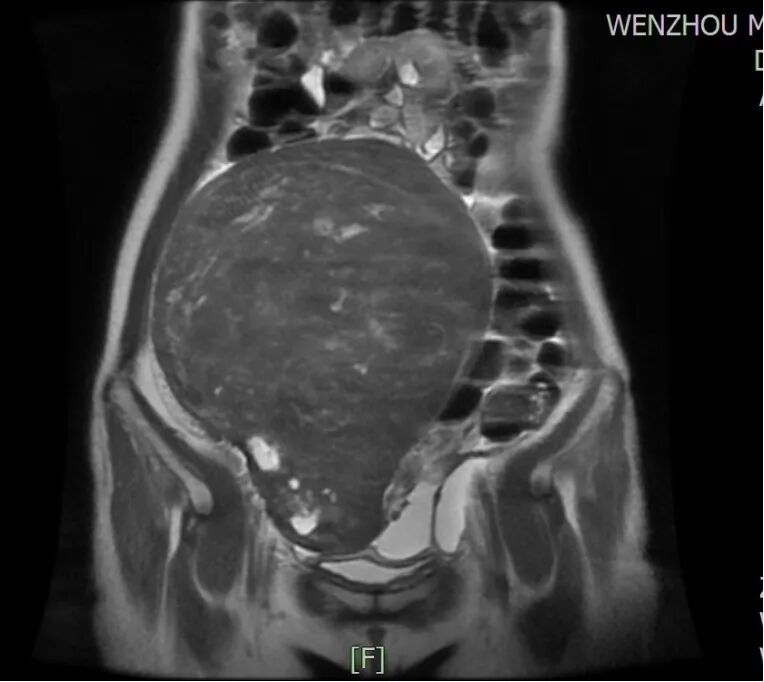

所幸经过B超检查提示“子宫多发肌瘤,肌层内见多个低回声团块,最大者位于宫底部,大小约203x103x184mm,边界清,突向浆膜外,内部回声不均匀”,磁共振检查也支持B超诊断。面对忧心忡忡的刘女士,陈主任苦口婆心,经过仔细询问病史结合辅助检查结果等,为她制定了“经脐单孔免气腹腹腔镜下子宫肌瘤剥除术”的手术方案。

1-2刘女士磁共振图片